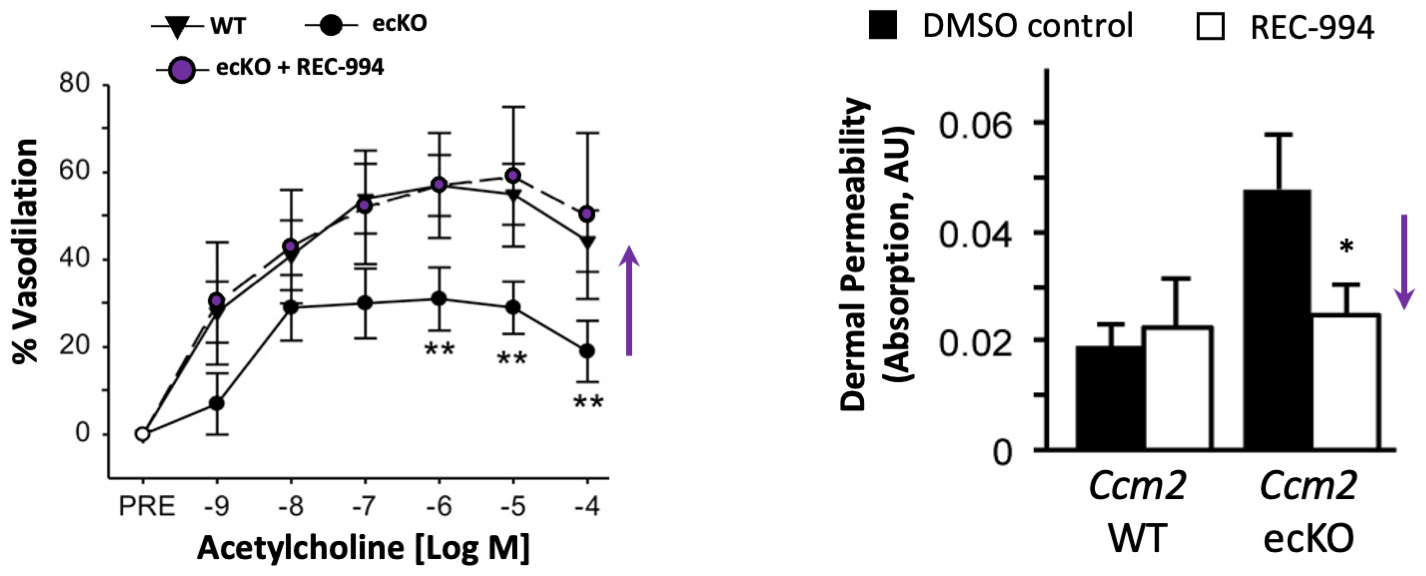

•Five phase 2 clinical-stage programs with multiple upcoming data readouts expected, including REC-994 in cerebral cavernous malformation (CCM) in Q3 2024, REC-2282 in neurofibromatosis type 2 (NF2) in Q4 2024, REC-4881 in familial adenomatous polyposis (FAP) in H1 2025, and REC-4881 in AXIN1 or APC mutant solid tumors in H1 2025

| | What’s more, the signs of AI-enabled point-solutions are already plentiful across our industry: •Protein folding •Scaled protein-ligand interaction prediction •Generative AI for chemistry for tractable targets •The FDA is already discussing the use of LLMs for program review •Major pharma companies are drafting regulatory filings like INDs by LLMs These facts lay out a clear future where efficiencies and improvements across the many current AI-enabled point-solutions will begin to combine into integrated ‘tech-stacks’ and workflows that will result in compounding improvements in our ability to drug historically undruggable targets, understand the underlying networks of biology with increasing fidelity, fast-follow newly validated biology, characterize disease in increasingly robust ways and ultimately deliver more, better medicines to patients to alleviate suffering at scale. The question is no longer whether this sort of future is before us, but when and who will lead it. Looking Back at 2023 and Before Reflecting back on late 2013 when Recursion was founded and how far we have come, it is simultaneously incredible and unsurprising to see where we are today. Recursion was then a Utah-based startup founded by two graduate students and a professor. Our first office was a conference room in the nearby University Research Park and our first laboratory was a converted storage room. Today, Recursion is a multinational, clinical-stage company leading the transition of BioTech into TechBio. We have over 500 employees, five clinical stage programs, one of the world’s largest biological and chemical datasets and two of the largest discovery collaborations in the industry with Roche/Genentech and Bayer. And in 2023, the opportunity ahead feels so much greater than it did in 2013, that in some ways it still feels like we are just getting started. In fact, from an internal perspective, 2023 felt like one of the best years in our history. In 2023 we achieved a lot of important milestones, and a lot of things we’ve been working to build, in some cases for years, really seemed to start hitting their stride, including: Pipeline •Five phase 2 clinical-stage programs with multiple upcoming data readouts expected, including REC-994 in cerebral cavernous malformation (CCM) in Q3 2024, REC-2282 in neurofibromatosis type 2 (NF2) in Q4 2024, REC-4881 in familial adenomatous polyposis (FAP) in H1 2025, and REC-4881 in AXIN1 or APC mutant solid tumors in H1 2025 •Completed a Phase 1 study for REC-3964 in healthy volunteers for the potential treatment of Clostridioides difficile (C. difficile) infection with a favorable safety and tolerability profile •Advanced our RBM39 program in homologous recombination proficient ovarian cancer and other solid tumors to IND-enabling studies •In-licensed a program (Target Epsilon) that emerged from our fibrosis collaboration with Bayer that represents a novel approach to treating fibrotic diseases with compelling early data |